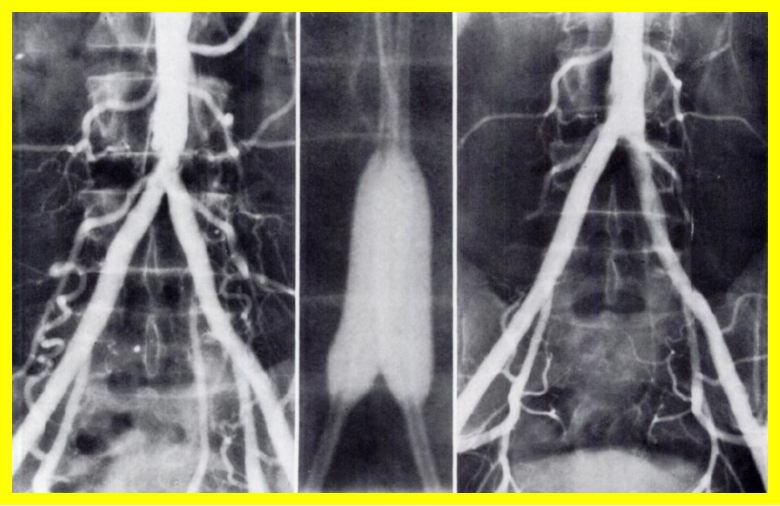

男性、58岁,间跛100米、慢性下肢缺血,病史3年

造影提示患者为长段闭塞,如果一期行腔内治疗,则累及肾动脉;所以行预置导管溶栓,后行支架术,血流重建效果显著。